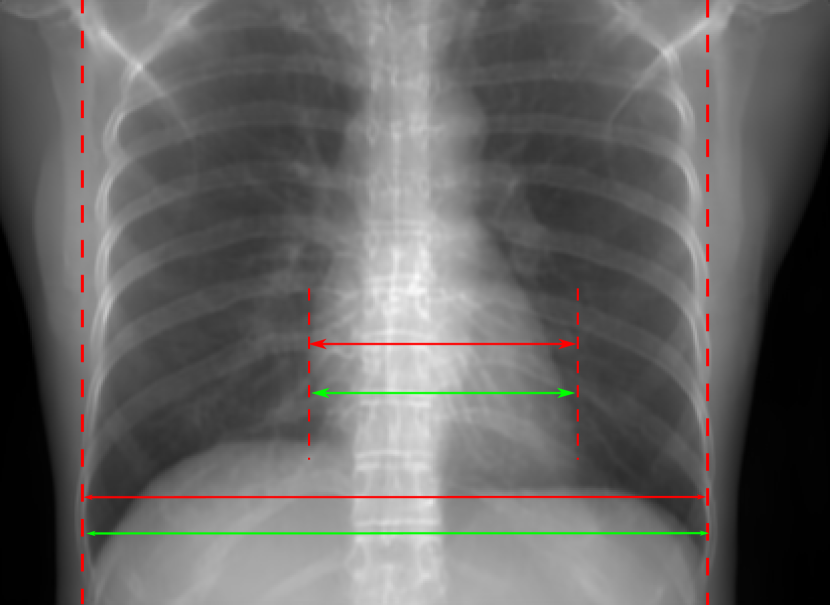

5.1 Chest Data

Refer to caption

(a) Reference

(b) 0superscript00^{\circ} perspective

(c) (b)-(a)

0.4237, -, -

0.4002, 17.01, 0.6532

Pix2pixGAN

(d) 0superscript00^{\circ} Cartesian

(e) 0&180superscript0superscript1800^{\circ}\&180^{\circ} Cartesian

(f) 0&180superscript0superscript1800^{\circ}\&180^{\circ} polar

0.4303, 7.08, 0.8535

0.4214, 5.37, 0.9098

0.4240, 3.83, 0.9536

(g) (d)-(a)

(h) (e)-(a)

(i) (f)-(a)

TransU-Net

(j) 0superscript00^{\circ} Cartesian

(k) 0&180superscript0superscript1800^{\circ}\&180^{\circ} Cartesian

(l) 0&180superscript0superscript1800^{\circ}\&180^{\circ} polar

0.4272, 10.92, 0.8222

0.4281, 9.37, 0.8424

0.4248, 8.12, 0.8859

(m) (j)-(a)

(n) (k)-(a)

(o) (l)-(a)

Figure 10: Perspective deformation learning in one exemplary patient case for chest X-ray imaging. The maximal horizontal cardiac diameter and the maximal horizontal thoracic diameter in (b) and (d)-(f) are indicated by the horizontal red lines, while those in the reference image (a) are green lines. The cardiothoracic ratio, RMSE, and SSIM for each image is displayed in its corresponding subcaption.

The results of one patient in chest X-ray imaging are displayed in Fig. 10, where the cardiothoracic ratio is assessed as an exemplary clinical application [32]. In the reference image (Fig. 10(a)), the maximal horizontal cardiac diameter (MHCD) and the maximal horizontal thoracic diameter (MHTD) are indicated by two green horizontal lines. Its cardiothoracic ratio is 0.4237. In the 0superscript00^{\circ} perspective projection image (Fig. 10(b)), all the anatomical structures can be visualized with fine resolution. However, due to perspective deformation, anatomical structures, e.g. the ribs and the spine, are deformed. The deformations are visualized better in the difference image Fig. 10(c). Compared with the ribs and the spine, the heart has less deformation as its location is closer to the isocenter. In Fig. 10(b), the MHCD and the MHTD are indicated by two red horizontal lines, while the green lines are those of the reference image. While the MHCD has changed little from 10.47 cm to 10.16 cm, the MHTD has changed considerably from 24.71 cm to 25.40 cm. As a consequence, the cardiothoracic ratio becomes 0.4002, which is below the normal range of 0.42 - 0.50 [32]. The result of learning perspective deformation from 0superscript00^{\circ} single view is displayed in Fig. 10(d), where the MHCD and the MHTD are 10.63 cm and 24.71 cm, respectively. The MHTD of Fig. 10(d) is the same as that of the reference image. This is also reflected by the difference image Fig. 10(g), where the lower ribs have small errors. However, the upper ribs as well as the spine still have considerable errors. The results of perspective deformation learning from 0&180superscript0superscript1800^{\circ}\&180^{\circ} views in Cartesian and polar coordinates are displayed in Fig. 10(e) and Fig. 10(f), respectively. The measured MHCDs and MHTDs in these two images are very close to the reference ones. Hence, their cardiothoracic ratios, 0.4214 and 0.4240 respectively, are close to the reference ratio as well. In the difference images (Fig. 10(h) and Fig. 10(i)), the errors of ribs and spine decrease as their boundaries are no longer apparently visible. Nevertheless, Fig. 10(i) has less error than Fig. 10(h), achieving the smallest RMSE value of 3.83. The quantitative evaluation of all the 162 testing datasets is displayed in Tab. II, where learning perspective deformation from two complementary views in polar coordinates achieves the least RMSE 4.98 and highest SSIM 0.9517, demonstrating the superiority of learning perspective deformation from two complementary views in polar coordinates.

The TransU-Net results are displayed in Figs. 10(j)-(l). Compared with their corresponding Pix2pixGAN results, the TransU-Net prediction images are more blurry, although the same perceptual loss is used. The error images in Figs. 10(m)-(o) indicate that TransU-Net reduces perspective deformation better with complementary views than a single view. The quantitative evaluation in Tab. II shows that TransU-Net cannot effectively reduce perspective deformation with a single view. With complementary views in both Cartesian and polar coordinate systems, TransU-Net achieves comparable performance, which is still considerably worse than that of Pix2pixGAN. The inferior performance of TransU-Net to Pix2pixGAN on the chest data is potentially caused by the repetitive nature of the segmental rib anatomy, which leads TransU-Net to be ineffective in extracting position-dependent features.